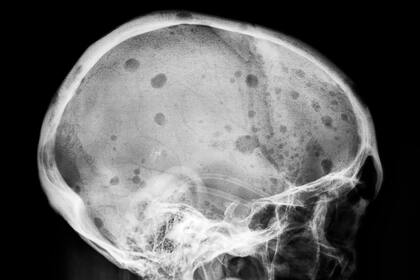

Los 36.000 estadounidenses que desarrollan mieloma múltiple cada año se enfrentan a una enfermedad que corroe los huesos, de modo que parece como si les hubieran hecho agujeros, dijo Carl June, de la Universidad de Pensilvania. Los huesos se colapsan. June ha visto pacientes que han perdido 15 centímetros de estatura.